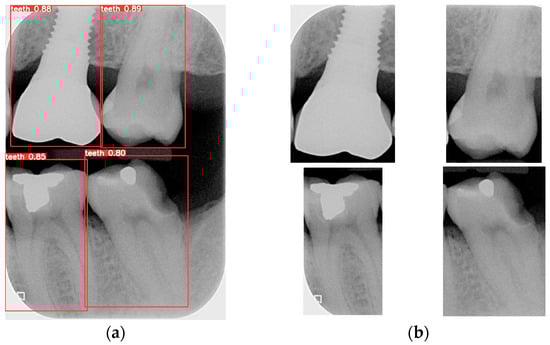

Object detection has been a challenging task in computer vision and deep learning. Traditional methods often require multiple steps, including region extraction, feature computation, and classification, leading to slow processing speeds and high complexity. However, recent advancements in deep learning have led to significant progress in object detection. YOLO achieves excellent accuracy and significantly outperforms traditional methods in image processing speed. Its uniqueness lies in detecting and locating objects in the entire image at once, without the need for excessive computation. YOLO is used to locate the teeth by finding the coordinates of each tooth in the BW. The BW is segmented according to these coordinates to produce an image of each individual tooth. Training the YOLO model requires a large amount of data for training and validation, with each piece of data distinguished from the target. The trained model is then applied to the entire database of BWs, identifying and labeling the position of each tooth. The BW is segmented to obtain individual tooth images after determining the coordinates of each tooth. Subsequently, the length and width data of the four teeth in the BW are used to segment each tooth, which is shown in Figure 8.

Figure 8.

The BW is segmented after single-tooth marking. (a) The result of the original image after the judgment. (b) Segmentation results.